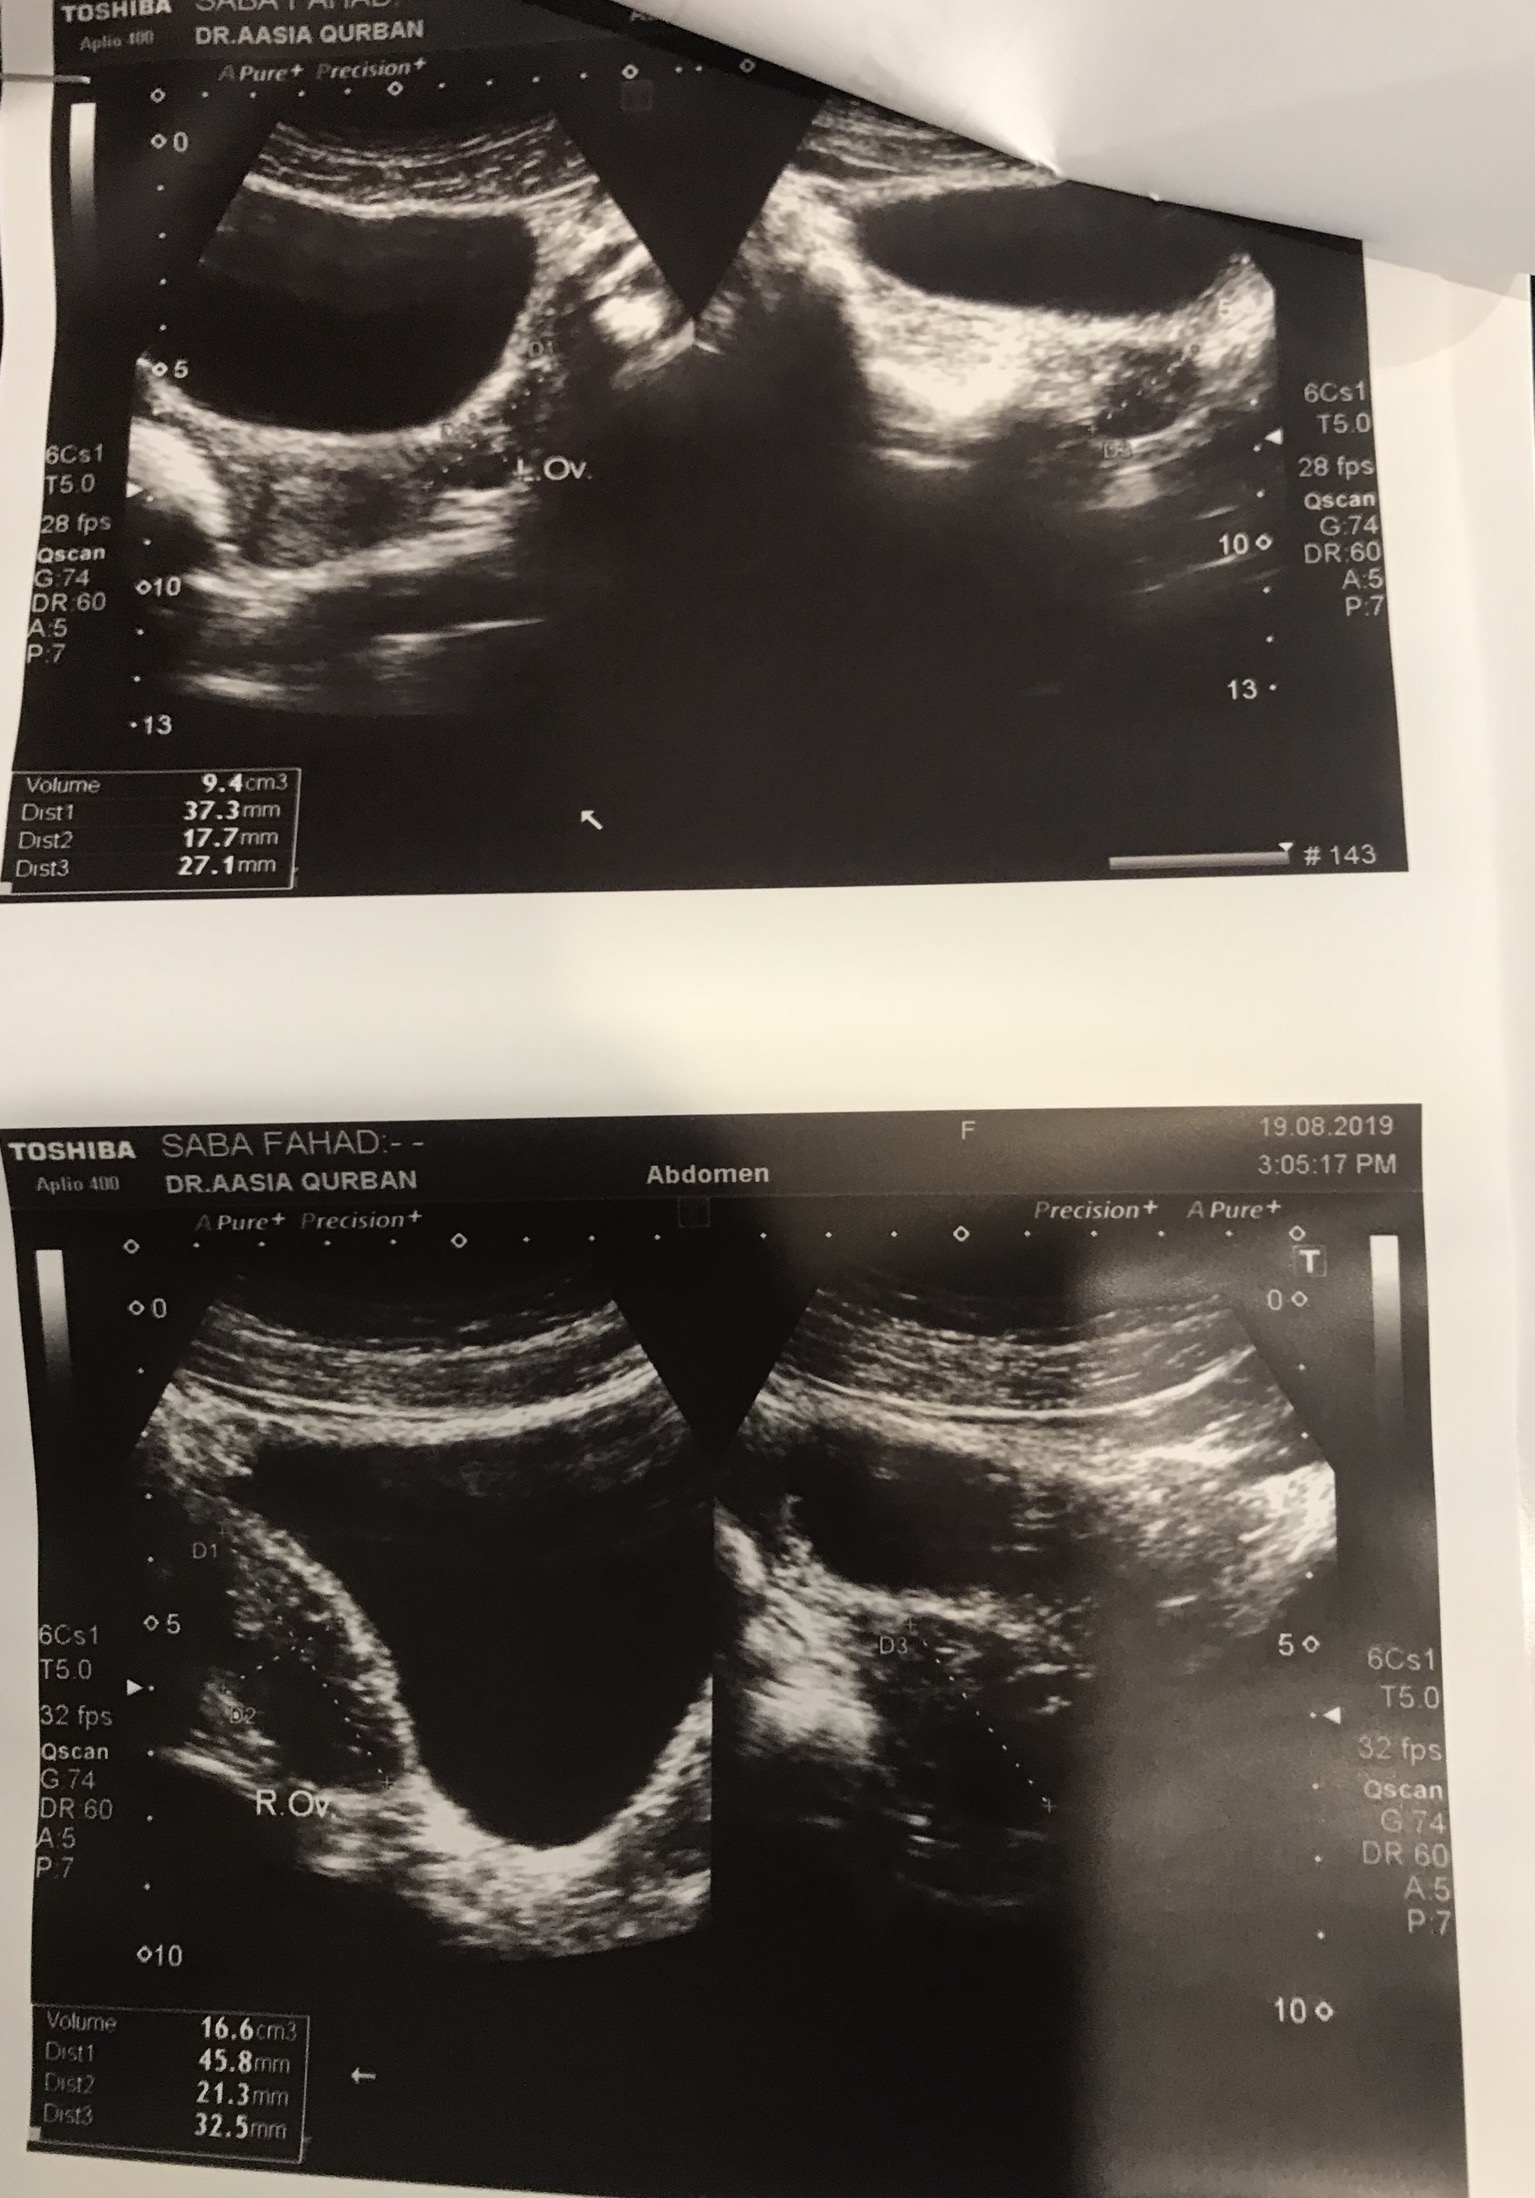

I am trying to conceive since 2 years. Doc told me that i have cysts but one doc said no cysts. Please see this ultrasound report and tell if i have cysts. Also please guide can I conceive with cysts?

You have cystic ovaries.

the pics r nt clear-anyways u shud take second opinion-as u r nt even clear about the status of ur cyst-for e.g. size, no etc...